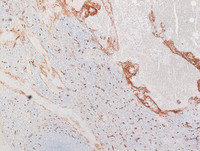

Figure 1: H&E images

Low power photomicrographs reveal a well demarcated tumor within the red pulp and uninvolved spleen at the periphery. Tumor shows proliferation of anastomosing vascular channels interspersed with dilated vascular and cyst like spaces.

Figure 3: CD31 and ERG (Ets-related gene)

Both CD31 (Image on the left) and ERG (Image on the right) are endothelial markers and typically stain the sinus lining cells in LCA, as expected.